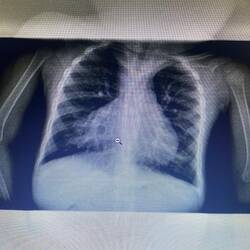

Nach einer Stunde Austausch über unsere Studienzeit und den Ablauf gehen wir zurück in die Klinik. Es sind nur einige wenige Meter, da das Wohnheim der Interns direkt am Gelände angrenzt. Die Dame mit dem Schlaganfall von gestern erwartet uns. Sie hat die vierstündige Fahrt von Litembo nach Songea zum CT überstanden. Die Bilder erhält Dr. Riziki auf dem kurzen Dienstweg. Bei WhatsApp zeigt er mir das CT-Bild vom Kopf der Patientin. Der Radiologe in Songea verschickt sie als Video-Nachricht, während er durch die Bilder klickt. Um zu verstehen, warum ich mich wundere, mache ich einen müden Ausflug in die Theorie der Radiologie. Ein Schlaganfall kann zwei Ursachen haben. Entweder blutet man aus einem Gefäß ins Gehirn, alle Areale dahinter werden demnach nicht mit Blut versorgt und es kommt zur bekannten Symptomatik. Oder ein Gefäß ist verschlossen, der Blutfluss also gestoppt. Auch hier ist das Hirnareal hinter diesem Verschluss nicht durchblutet und stirbt ab. Eine frische Blutung ist in einem CT-Scan leicht zu sehen. Möchte man Gefäße in einem CT-Scan darstellen, so benötigt man Kontrastmittel, welches die Gefäße sichtbar macht. Um zu verstehen, wo das Gefäß also verschlossen ist und welche Regionen des Gehirns in Mitleidenschaft gezogen sind, ist ein Kontrastmittel-CT indiziert. (In Deutschland gehört dies zur Routine-Diagnostik bei einem akuten Schlaganfall). Die Patientin, die 4 Stunden zum CT gefahren wurde und 4 Stunden zurück, erhält aber nur eines ohne Kontrastmittel. Wir sehen auf der Aufnahme: Es ist keine Blutung. Die gesamte rechte Hirnhälfte ist untergegangen. Ein Pflegefall für die Familie. Dr. Riziki meint, es bestehen Chancen, dass die Patientin in einigen Monaten sogar wieder laufen könne. Ich bin mir allerdings sicher, dass ein solches CT-Bild absolut nicht dazu passt. Auch als ich nachfrage, warum kein Kontrastmittel gegeben wurde, merke ich, dass Dr. Riziki schlicht nicht routiniert ist. Er gibt ehrlich zu, dass er weder Radiologe noch Neurologe ist und dachte, dass Kontrastmittel schädlich sei. Die Qualität dieser Versorgung ist alles andere als gut. Die Familie ist jedoch dankbar und erleichtert, dass die Diagnose bestätigt wurde. Verrückt, denke ich. Der Mann der Patientin bedankt sich sogar bei mir, dass ich ebenfalls an der Behandlung beteiligt bin. Ich nehme seinen Dank an, da es unfreundlich wäre, es nicht zu tun, wenn ein Familienoberhaupt dies hier ausspricht. Aber ich sage Dr. Riziki, dass er ausrichten soll, dass ich an diesem Fall lerne und nicht behandle. Für Angehörige ist es eine Ehre, wenn weiße Menschen an der Behandlung beteiligt sind. Ein Kult um weiße Menschen, den ich nie verstehen werde.